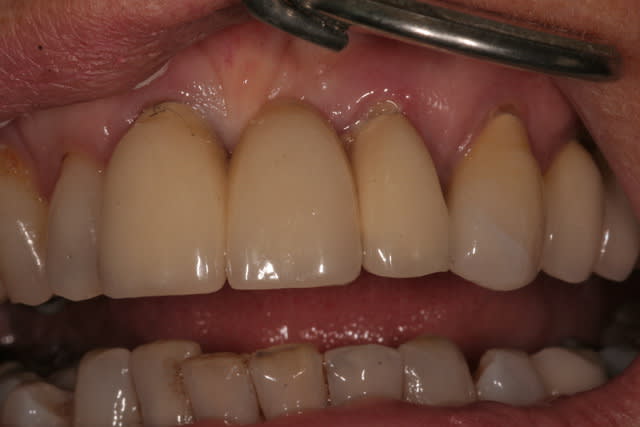

femme, 62 ans, santé RAS, qui arrive avec un bridge (fait par le confrère que j'ai remplacé il y a 2 ans) 11-(21)-22 mobile. 22 fracturée, je dépose, fais un provisoire.

All-on-8/10 en haut...ou complet...sérieusement tout est moche la haut.

Ce qui est sûr, c'est que je n'irai pas mettre un bridge sur cette latérale. Et même une couronne unitaire, j'hésiterais: trop grêle. Pas de ferule effect, racine trop courte. Bref tout pour plaire.